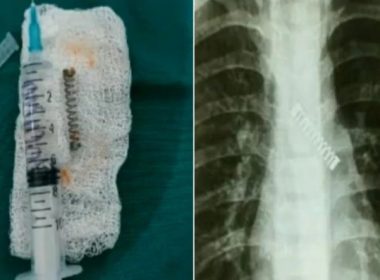

Детето подоцна било префрлено во Националниот институт за респираторни и еколошки болести на итна помош Кашлицата обично е предизвикана од настинка и децата развиваат кашлица во просек околу осум пати […]